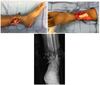

Which of the following conditions is a relative CONTRAINDICATION for use of the flap in the image shown for reconstruction of an 8 x 10-cm anterior ankle wound?

The correct response is Option D.

Hypertension does not preclude the use of any fasciocutaneous flaps in the lower extremity.

Diabetes mellitus can be associated with peripheral vascular disease, but by itself, would not prevent successful use of the reverse sural artery flap for foot or ankle reconstruction. Appropriate preoperative workup would include noninvasive ultrasound study of the lower extremity vasculature to prove the peroneal artery was patent.

Vascularized flaps, including the reverse sural artery flap, provide excellent coverage for foot/ankle wounds, including those with underlying osteomyelitis. Effective treatment would necessitate adequate debridement and antibiotic therapy as part of the reconstructive paradigm.

The distally based sural artery flap receives its blood supply from a few sources, the most robust of which are perforators from the peroneal artery. The most distal of these perforators arise between 4 and 7 cm proximal to the lateral malleolus. Additional perfusion arises from neurocutaneous perforators from the sural nerve and venocutaneous perforators from the lesser saphenous vein.